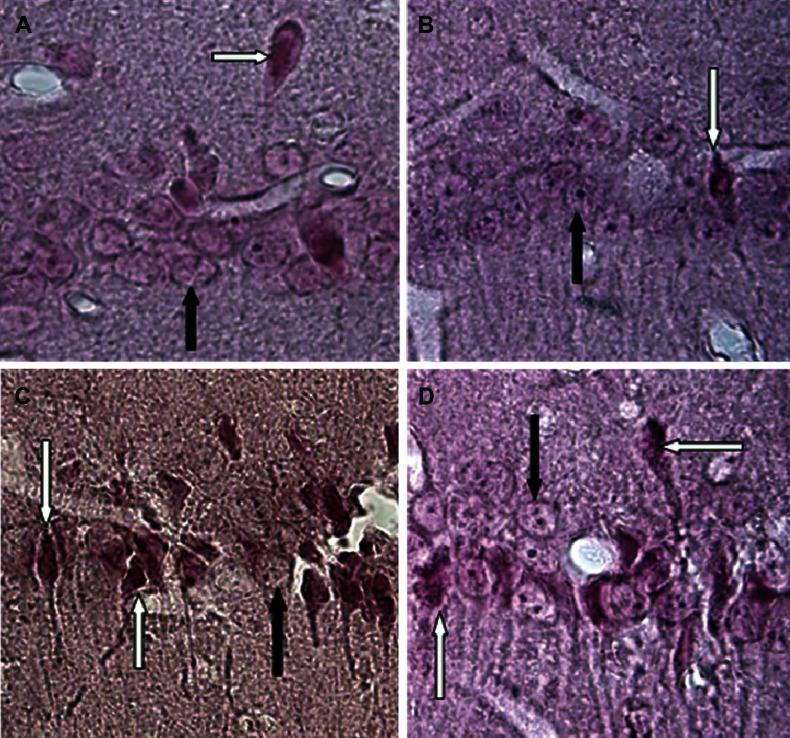

Results showed that pretreatment with carnosic acid can reduce cellular death in the cornu ammonis 1 (CA1) region of the hippocampus in the lesion+CA group, as compared with the lesion group.

结果表明,与损伤组相比,损伤+CA 组中 CA 的预处理可以减少海马 CA1 区的细胞死亡。